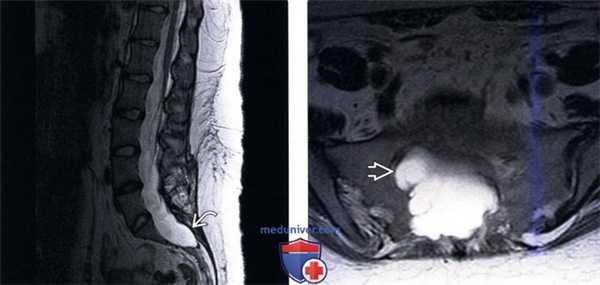

(Слева) Т2-ВИ, сагиттальная проекция (синдром Лойса-Дитца) пояснично-крестцового отдела позвоночника: вдавление задних покровных пластинок тел позвонков и расширение терминального отдела дурального мешка. Обратите внимание на выраженное ремоделирование и эрозивные изменения крестца.

(Справа) Аксиальное Т2-ВИ (синдром Лойса-Дитца) подтверждает выраженное расширение дурального мешка с формированием дивертикула, продолжающегося в близлежащее крестцовое отверстие. Обратите внимание на ремоделирование задней стенки позвонка и костных стенок спинномозгового канала.